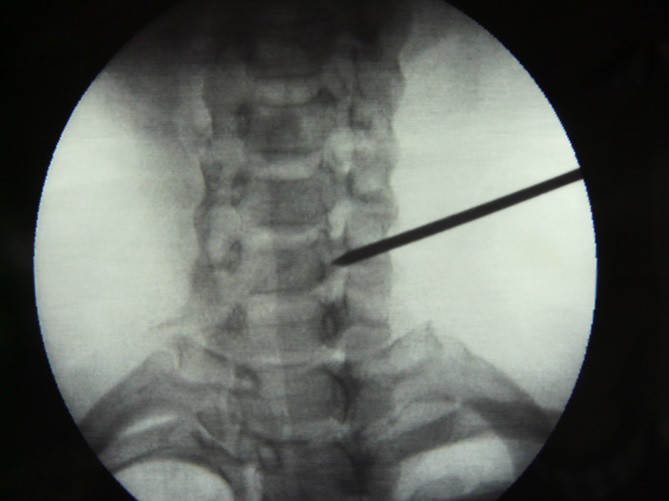

Fig.2. Se retira unos 2 mm de la estructura ósea y se administran 2 ml de medio de contraste.

3/6

Fig.4. Introducción de la aguja espinal.

5/6